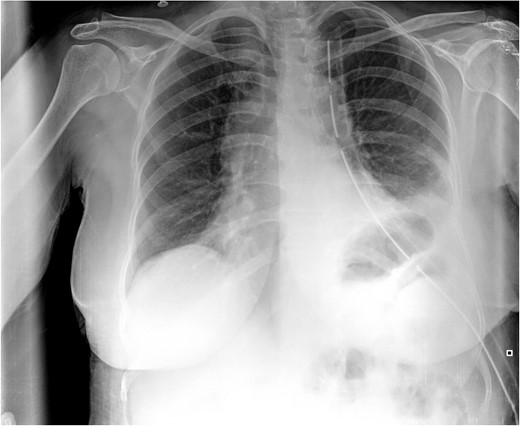

Postoperative CXR. It shows partial lung expansion with apical chest tube.